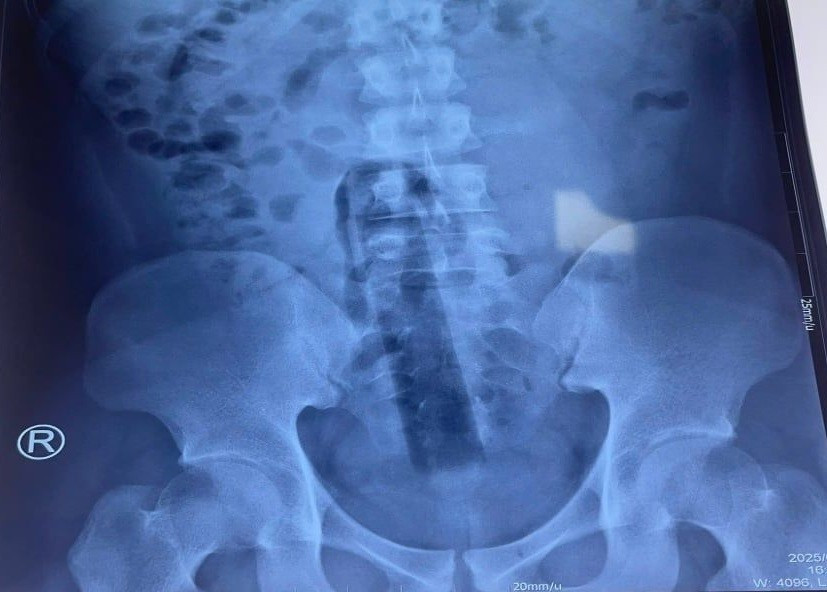

Hình ảnh X-quang cho thấy dị vật nằm sâu trong khung chậu. BS.CKII Đặng Khải Toàn – Phó Trưởng khoa Ngoại Tổng hợp, cho biết: “Do đoạn cán cây lau nhà không có điểm chặn bên ngoài và không phải vật dụng chuyên dụng cho cơ thể người, nó đã mắc kẹt tại vị trí sâu, gây đau và nguy cơ biến chứng cao. Việc lấy dị vật ra không thể thực hiện bằng phương pháp thông thường hoặc nội soi qua ngả hậu môn”.